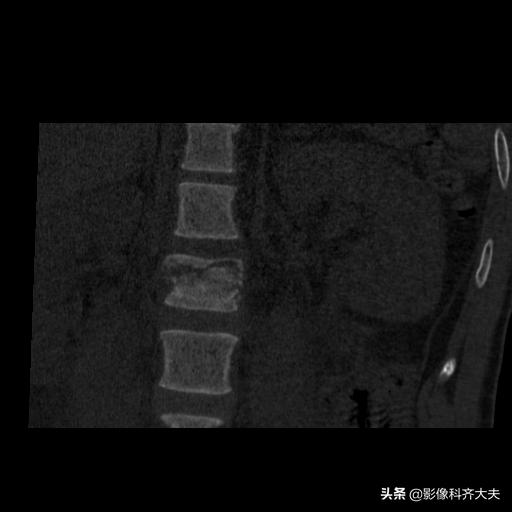

腰二横突骨折

矢状面重建